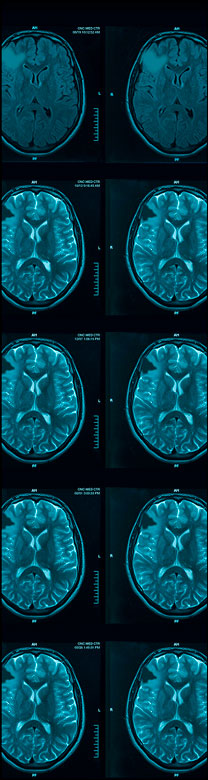

VORANIGO (40 mg tablets) is a prescription medicine used to treat adults and children 12 years of age and older with certain types of brain tumors called astrocytoma or oligodendroglioma with an isocitrate dehydrogenase-1 (IDH1) or isocitrate dehydrogenase-2 (IDH2) mutation, following surgery. Your healthcare provider will perform a test to make sure that VORANIGO is right for you. It is not known if VORANIGO is safe and effective in children under 12 years of age.